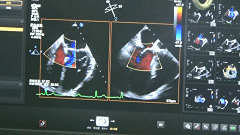

彩色超声多普勒缺认反流明显减少、夹合效果良好

完全在超声引导下完成二尖瓣夹的定位、瓣叶抓取和二尖瓣夹的释放